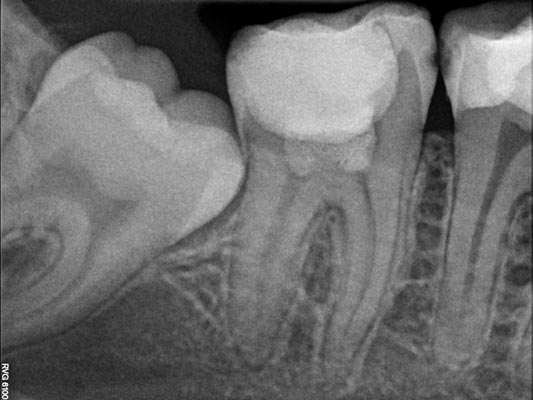

Los tratamientos en diente vital se realizan en casos de caries profundas, cuando es posible mantener la pulpa dental viva. Dependiendo de cada situación, el tratamiento puede consistir en una pulpotomía parcial o total, o bien en un recubrimiento pulpar directo o indirecto, con el objetivo de preservar la vitalidad del diente. Hasta hace pocos años, este tipo de tratamientos estaba indicado principalmente en paciente jóvenes. Sin embargo, en la actualidad la Sociedad Europea de Endodoncia respalda su uso también en pacientes adultos, siempre que se cumplan los criterios clínicos adecuados.

Imágenes: Caries profunda - Pulpotomía - Control a 2 años